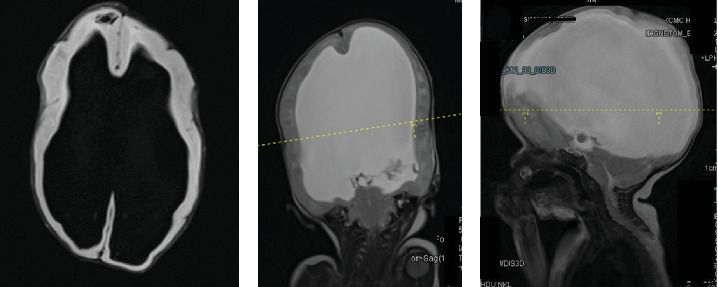

Meningomyelocele and meningocele are types of neural tube defects, which are congenital abnormalities of the spine and spinal cord. These conditions are frequently encountered by pediatric neurosurgeons worldwide and represent a significant public health concern due to their association with a range of collateral conditions, other malformations, and increased morbidity. While many cases can be identified during prenatal ultrasound screenings, this is often challenging in resource-limited settings with poor health-seeking behaviors. Surgical intervention is the primary treatment for these defects, and while various methods are described in the literature, larger defects require complex flaps and techniques, with limited options available. Beyond early surgical intervention, patients require lifelong care involving multidisciplinary medical teams.

Abstract Image